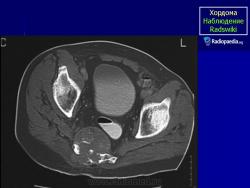

Случай 2: sacrococcygeal

Случай 8: sacrococcygeal

Случай 10: sacrococcygeal

Случай 12: sacrococcygeal

Случай 15: рецидивирующий sacrococcygeal